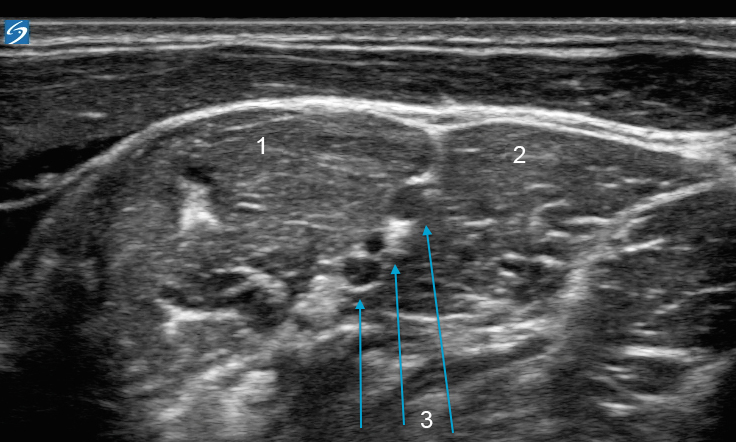

X-Porte:肌间沟神经图像

前斜角肌

中斜角肌

神经束